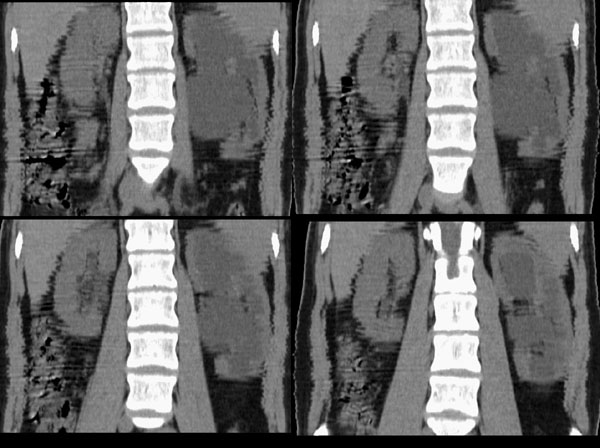

左肾区囊肿冠、矢状重建:

左侧肾盂、肾盏扩张,肾盂输尿管移行部突然狭窄,未见明显占位及高密度结石影,体检发现,考虑:先天性肾盂输尿管移行部狭窄。(原因多方面,有先天缺陷造成移行部结构异常或因为迷走血管、纤维索条引起肾盂输尿管的压迫扭曲所致。)大剂量ivp或肾盂造影有助于显示输尿管狭窄部位及形态。